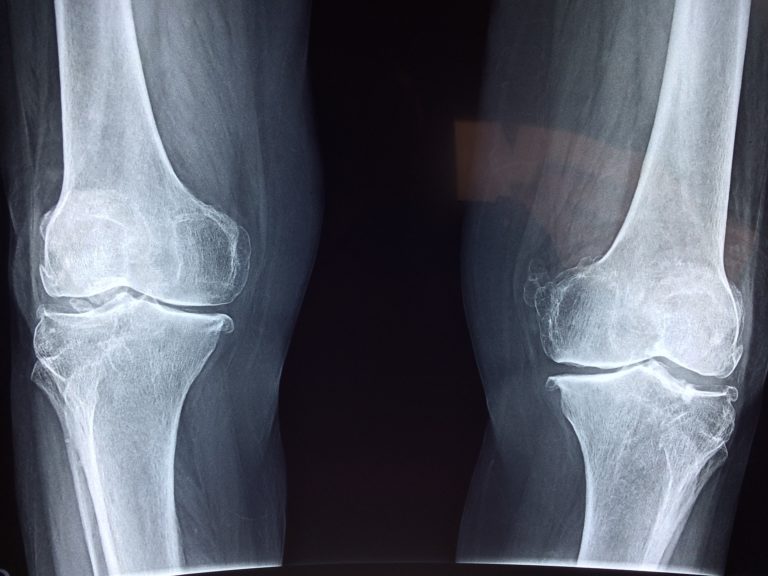

Porady na obrzęki i ból kolan:

Opuchnięte kolano może wskazywać na różne problemy, dlatego przy utrzymujących się lub pogarszających się stanach zaleca się wizytę u lekarza. Oto mój sprawdzony przepis, skuteczny na ból, obrzęk, a nawet gromadzącą się w kolanie wodę. Można go przygotować w domu w minutę.